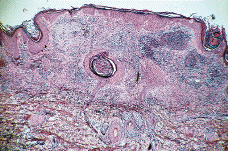

Paciente masculino de 50 años de edad con el único antecedente personal de interés de hipertrigliceridemia controlada con dieta. Consultó al Servicio de Dermatología en el año noventa por presentar lesiones papulotuberosas, algunas pustulosas, en ambos codos, de varios meses de evolución (Figs. 1 y 2). La analítica de rutina solicitada, salvo los triglicéridos, fue rigurosamente normal. El cultivo de hongos, bacterias, tinción y cultivo para micobacterias y la prueba de Mantoux resultaron negativos; la radiografía de tórax sin alteraciones. En el estudio histológico de una de las lesiones de antebrazo se observó necrosis en dermis con infiltrado abcesiforme y algunas células linfohistiocitarias (Fig. 3); no se llegó a un diagnóstico definitivo. Un mes después apareció en pierna izquierda una lesión ulcerosa de 6-7 cm de diámetro con necrosis central y borde eritematovioláceo, lo que orientó hacia el diagnóstico definitivo de PG (Fig. 4). Se inició entonces tratamiento con corticoesteroides por vía oral (prednisona, 60 mg/día) con lo que se consiguió la reepitelización progresiva de la lesión de la pierna y el aplanamiento de las lesiones de antebrazos. El estudio del aparato digestivo para descartar la presencia de enfermedad inflamatoria intestinal (EII) resultó negativo, pero se detectó la presencia de una úlcera en estómago y duodeno que obligó a suspender la corticoterapia oral; esto originó empeoramiento y la aparición de un nuevo brote de lesiones.

FIG. 3.--A: Estudio histológico con hematoxilinaeosina: bajo una epidermis acantósica se observa en dermis foco de necrosis con infiltrado abcesiforme de predominio de neutrófilos y algunas células linfohistiocitarias. B: Imagen a detalle del infiltrado abcesiforme en dermis.

En la PG no existen datos de laboratorio específicos y la histología también es inespecífica. La célula fundamental en el infiltrado inflamatorio es el neutrófilo. En general la epidermis y la dermis superficial suelen estar ulceradas y necróticas y existe un denso infiltrado abcesiforme de neutrófilos que suele extenderse hasta hipodermis; la epidermis del borde de la úlcera se muestra hiperplásica, lo que es más evidente en lesiones evolucionadas y el infiltrado será tanto más crónico, linfocitario, cuanto más nos alejemos del borde activo de la lesión. Su y cols. (8) reconocen tres patrones histológicos dependiendo del lugar de la biopsia.